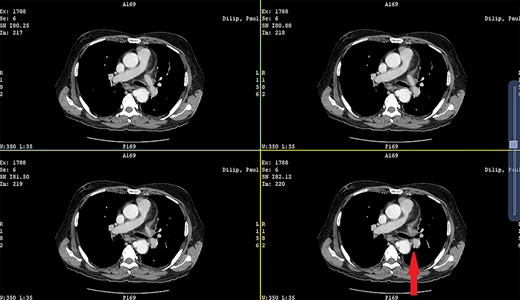

Patient 1: a 52-year-old woman, non-diabetic, non-hypertensive, was referred to the emergency with a history of large-volume, frank hematemesis (four episodes in 3 days). Positive history included recurrent cough for the past 1 year and low-grade fever for 3 months. No history of dysphagia, jaundice, abdominal distension, pain abdomen or altered sensorium. No history of chronic medications (oral anticoagulants or anti-platelets), analgesic intake or any substance abuse. She had received four units of packed red cells at an outside facility prior to admission. She was conscious, oriented, hemodynamically labile (heart rate: 110/min; BP: 86/60 mm Hg) with mild fever (99°F). General survey revealed obvious pallor. All other system examinations were within acceptable limits. Her hemoglobin (Hb) was 7.3 gram%, total leukocyte count (TLC) was 6400 cells/mm3, total bilirubin was 1.31 mg/dl and total protein was 4.75 gram%. An urgent UGI endoscopy revealed an opening in the posterior wall of the lower third of the esophagus, with a diverticulum. Inflammatory changes were noted in the diverticulum (Fig. 1). Contrast-enhanced computed tomogram (CECT) revealed erosion of the pouch into the thoracic aorta (Fig. 2), and a diagnosis of AEF with acute UGI hemorrhage was made.

CECT showing the descending thoracic aortic aneurysm; the red arrow shows the communication of the aneurysm with the esophagus.

Patient 2: a 48-year-old hypertensive, non-diabetic gentleman, presented to the emergency with one episode of massive hematemesis. There was no history of dysphagia, jaundice, abdominal distension, pain abdomen or altered sensorium. Past history was significant for percutaneous coronary intervention with two drug-eluting stents performed 3 years ago, for which he was on aspirin. He had normal mentation, his BP was 90/60 mm Hg and his heart rate was 120/min. A general survey revealed pallor and rest of the systemic examination was normal. His Hb was 6.1 gram% and TLC was 6300 cells/mm3. Liver function tests, coagulation parameters, renal function and electrolytes were normal. Chest X-ray was unremarkable. He was initially resuscitated with intravenous fluid, packed red blood cells and a proton-pump inhibitor infusion. An urgent UGI endoscopy revealed a large depressed ulcer with a red spot located in the middle third of the esophagus. A diverticulum was seen in the lower end of the ulcer (Fig. 7). An endoscopic clip was applied to the margin for ease of identification. CECT thorax revealed a 6 cm saccular thoracic aortic aneurysm distal to the left subclavian artery, eroding into the esophagus (Fig. 8).